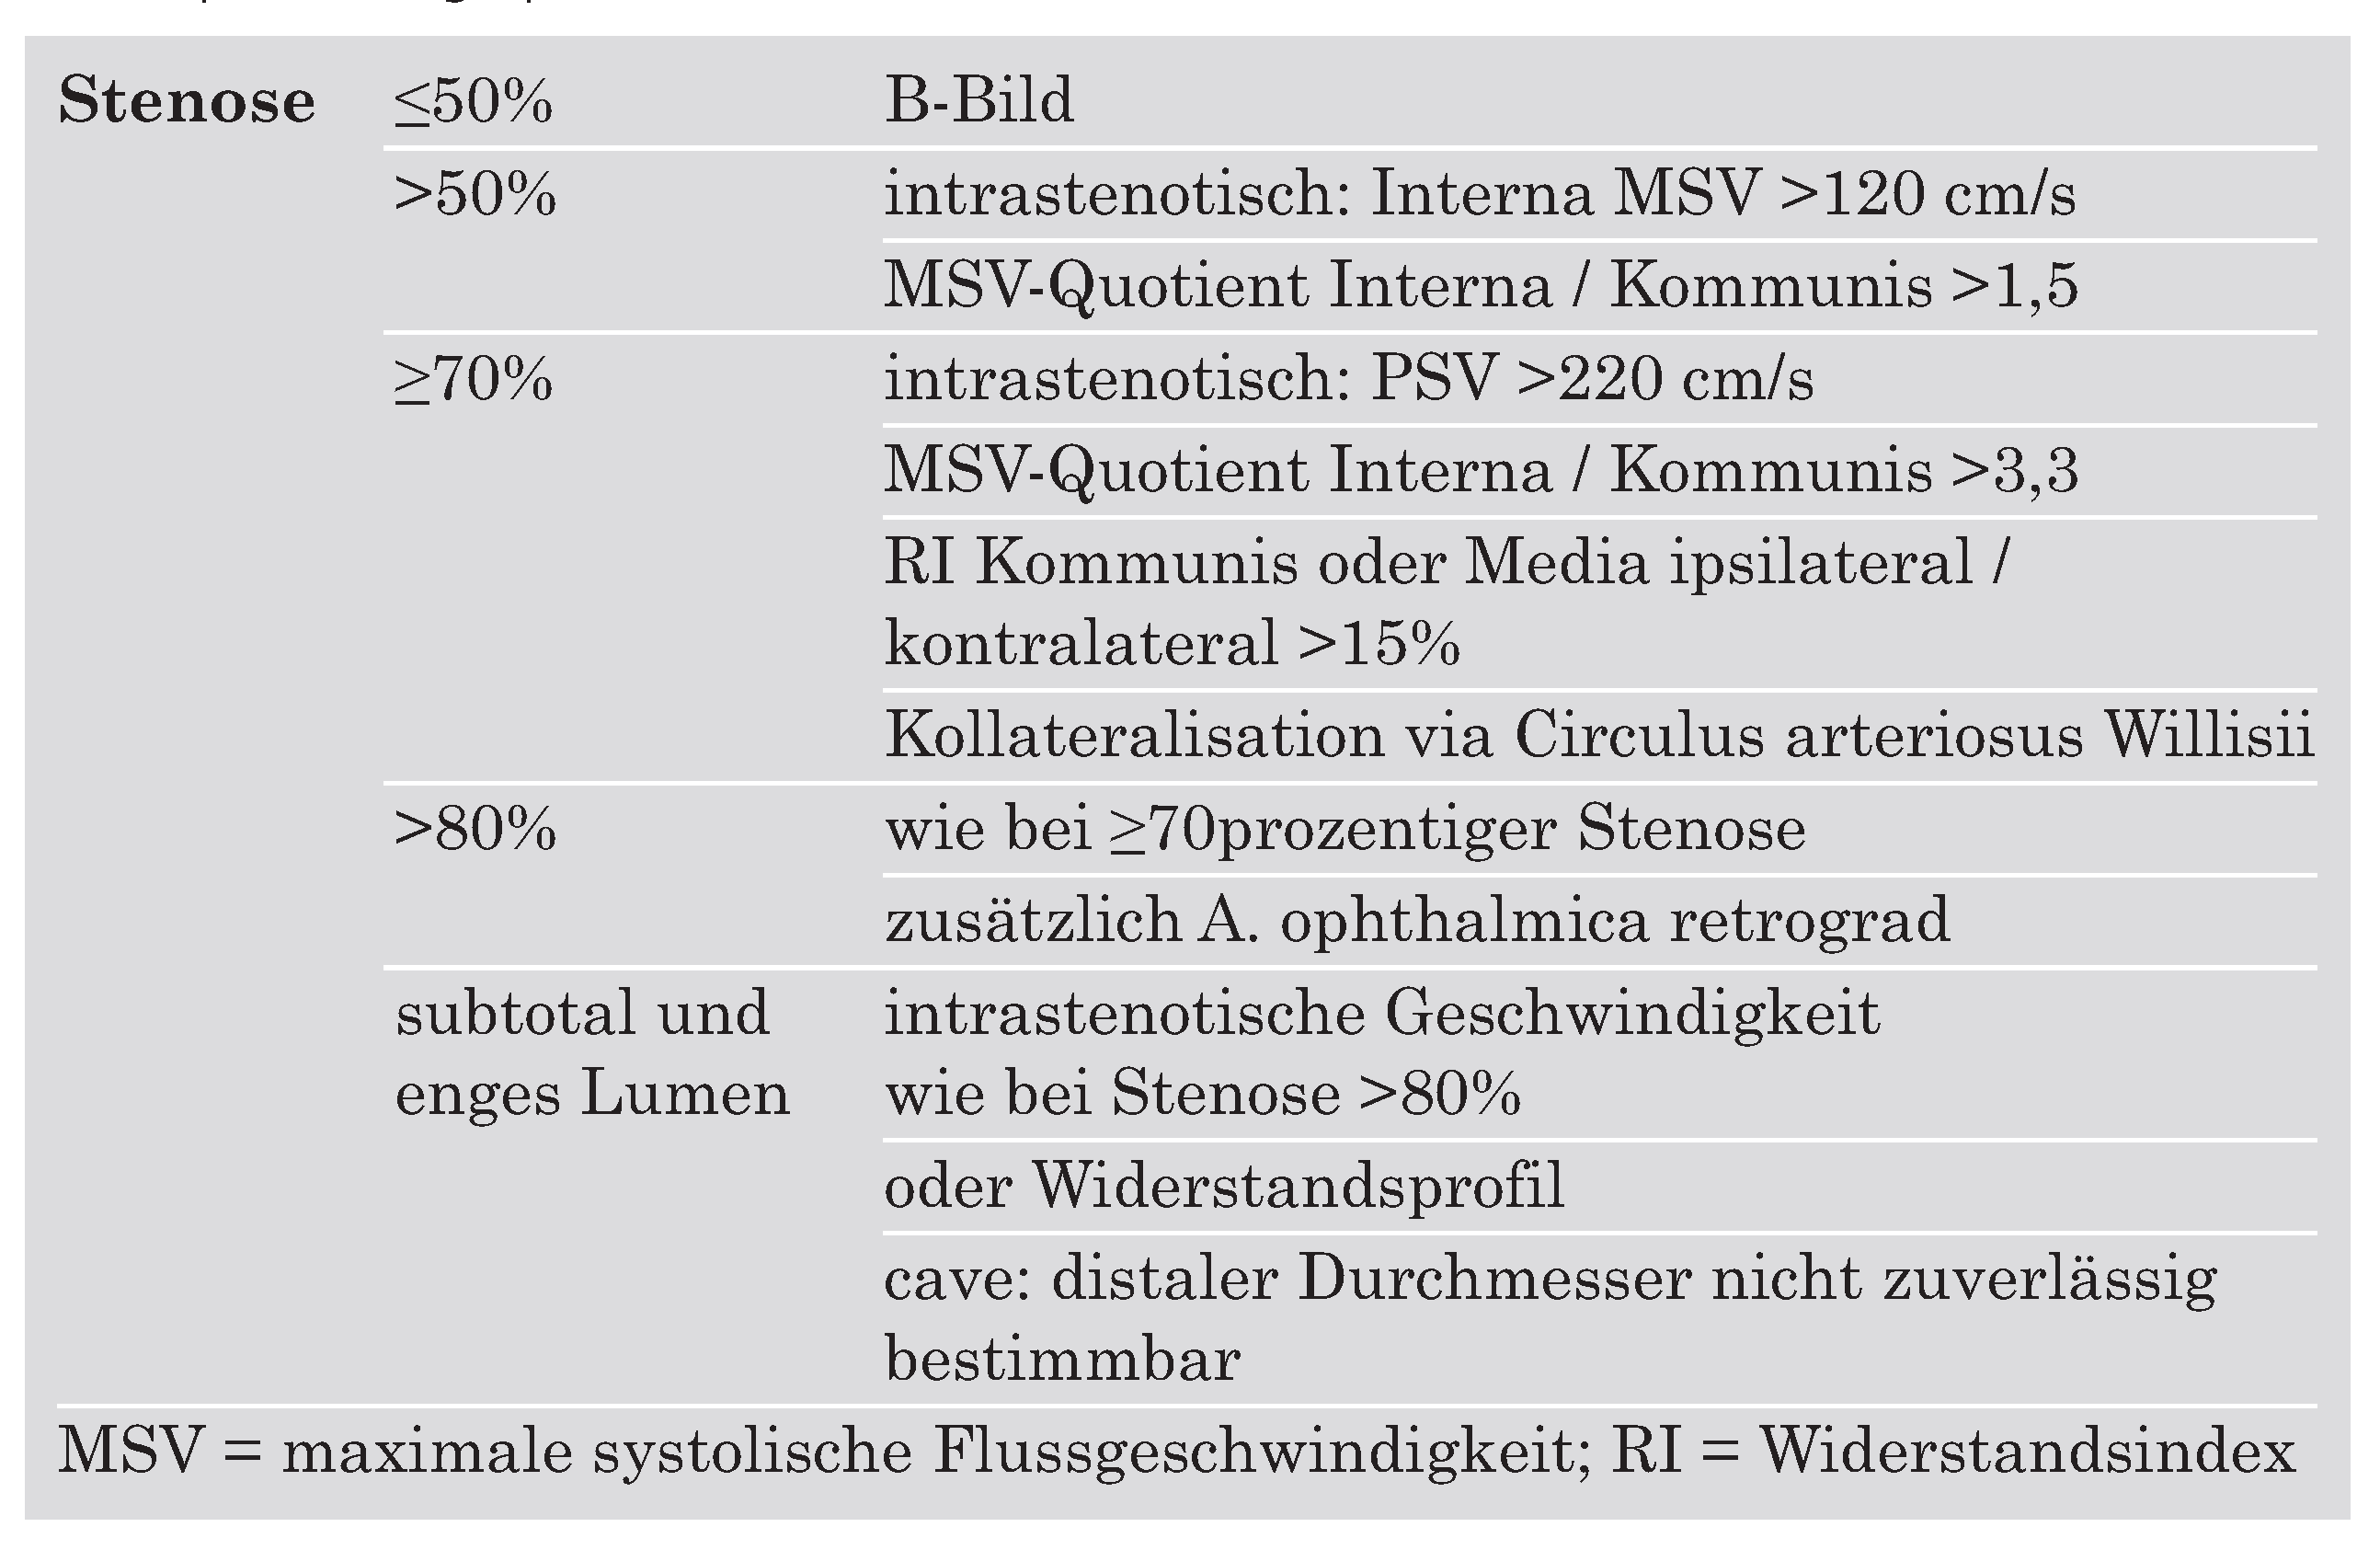

Ultrasonographische Verfahren